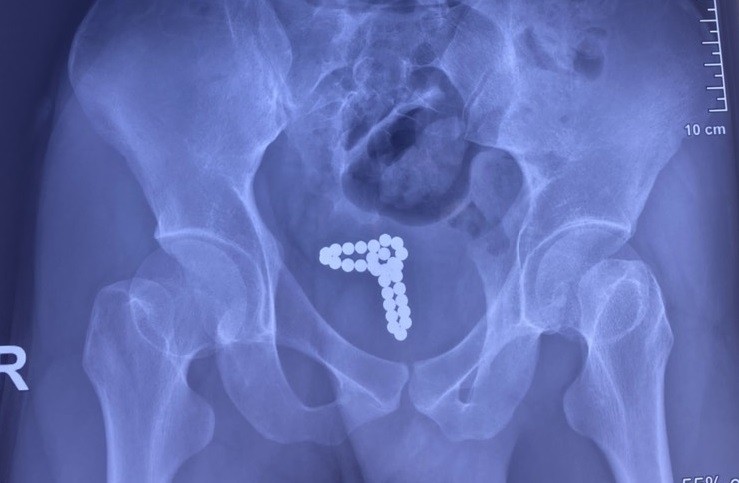

Ngày 28/2, thông tin từ Bệnh viện Nhân Dân 115 cho biết, tại đây vừa tiếp nhận và can thiệp cho một trường hợp bị dị vật niệu đạo rất hy hữu. Bệnh nhân là nam thanh niên N.B.T (22 tuổi, ngụ tại TPHCM) nhập viện cấp cứu trong tình trạng tiểu ra máu.

Trước đó, nam thanh niên đã dùng chuỗi bi kim loại nhét vào bộ phận sinh dục để “tự sướng”. Trong lúc cao trào khoái cảm thì chuỗi bi kim loại bất ngờ tuột vào niệu đạo không thể tự lấy ra khiến bệnh nhân đi tiểu ra máu phải nhập viện cấp cứu.

Tại Đơn vị Nam khoa, qua thăm khám lâm sàng và làm các xét nghiệm, chụp X-quang bụng, các bác sĩ xác định dị vật là chuỗi hạt kim loại có từ tính dính với nhau thành chuỗi đang nằm trong bàng quang của người bệnh. Dị vật gây tổn thương bàng quang là nguyên nhân khiến bệnh nhân tiểu ra máu.

Sau hội chẩn, các bác sĩ đã tiến hành phẫu thuật mở bàng quang để gắp dị vật. Qua các thao tác chuyên môn theo vết mổ khoảng 2cm, các bác sĩ đã lấy ra 30 viên bi kim loại nhiều màu sắc, mỗi viên có kích thước khoảng 5mm dính với nhau thành chuỗi. Sau phẫu thuật, tình trạng sức khỏe của bệnh nhân đã ổn định.